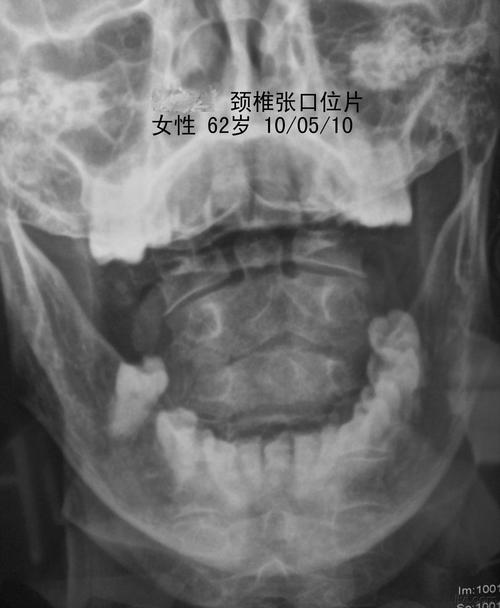

颈椎张口位报告模板

颈椎张口位报告模板,颈椎张口位正常模板

颈椎正侧位不易于观察寰,枢椎情况,通过张口位拍片,可以观察寰,枢椎有

颈椎张口位

颈椎张口位片.jpg

观察有无寰枢关节脱臼,齿状突骨折或缺失(张口位片);第七颈椎横突有

二,颈椎张口位片

颈椎张口位正常模板

颈椎张口位x片

张口位颈椎片报告模板